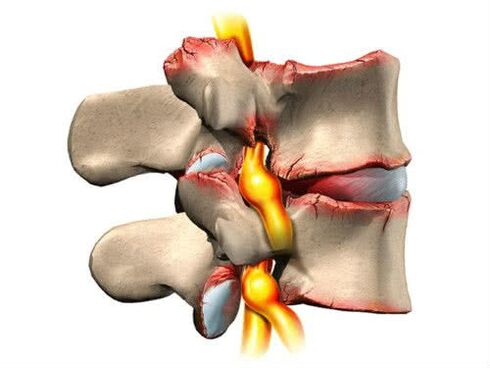

- Discogenic radiculitis stage.The fibrous ring begins to slowly deform (cracks and protrusions appear).The pain becomes sharper and more sudden, the discomfort becomes more noticeable.A symptom such as "lumbago" appears, the limbs begin to go numb;

- Vascular-radicular stage.The fibrinous ring completely loses its shape.From this point on, hernias can form.X-rays are very informative.Subjective feelings of patients are expressed (pain, sharp attacks of pain, constant discomfort).Frequent muscle spasms appear, and performance drops sharply.If nerve fibers suffer, then the first signs of dysfunction of internal systems are inevitable;

- As the height of the vertebrae decreases, friction begins between them.Osteophytes may occur as a compensatory mechanism.These are specific bone growths that help strengthen the area where the friction was most intense.But osteophytes can cause inflammatory processes in the surrounding soft tissues, worsening the pathological picture.